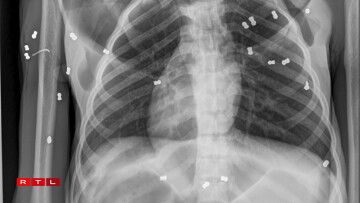

Dem Afeweibche geet et hire Retter no mëttlerweil besser an dat trotz de 74 Kugelen, déi bei der Röntgen an engem Spidol gezielt goufen. D’Déier krut den Numm “Hope” (Hoffnung). Schätzungen no gëtt et op Sumatra an der Nopeschinsel Borneo am Ganzen ongeféier 110.000 Orang-Utanen. D’Mënschenafe sinn a Gefor, well se duerch d’Ofholze vum Dschungel fir de Palmenueleg hire Liewensraum verléieren.